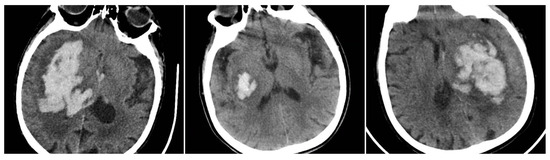

The Blend Sign (BS) was recorded when a well-defined hypoattenuating region directly abutted a hyperattenuating area within the same hematoma, differing by ≥18 HU, without the hypodense portion being fully encapsulated by the hyperdense region (BS = 1 if present, otherwise 0) (Figure 1) [9].

Figure 1. (Left) Hematoma showing Black Hole and Blend Signs; (middle and right) other examples of Blend Signs.

The Black Hole Sign (BHS) refers to a discrete, well-defined hypoattenuating region fully enclosed within a hyperdense clot with ≥28 HU difference and no continuity with normal parenchyma (BHS = 1 if present, otherwise 0) (Figure 2) [10].